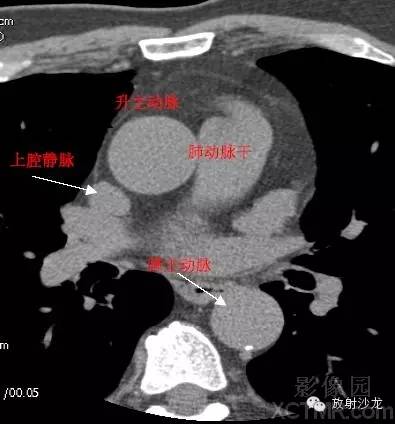

A.Aorta-Ascending Aorta升主动脉

SVC –Superior Vena Cava上腔静脉

PA -Pulmonary Artery肺动脉